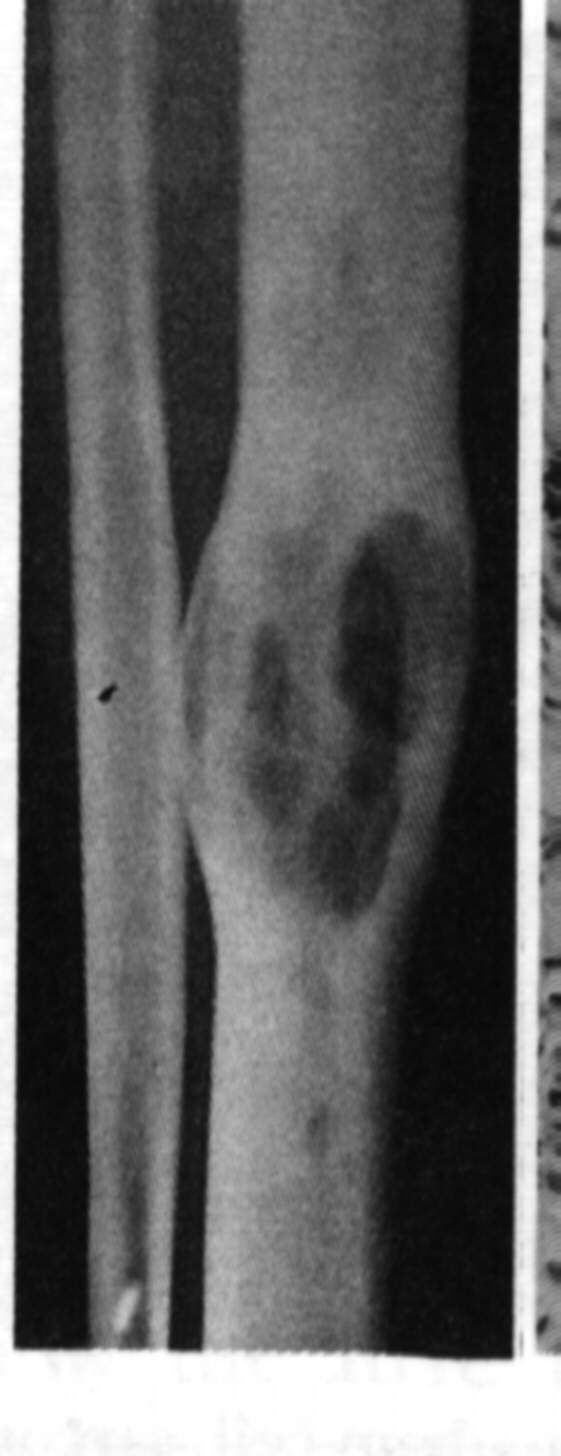

Imaging

X-rays show a large destructive lesion that often involves the metaphysis and particularly the diaphysis (unlike osteosarcoma), they may be lytic, or show variable amounts of new bone formation. The periosteum may be lifted off in many layers, giving the uncommon but characteristic onion skinning. There is usually a large soft tissue component,(CT and MRI). A bone scan/PET is necessary to look for other bone involvement.